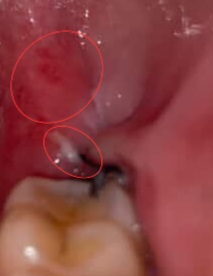

มีใครเคยผ่าฟันคุดแล้วแผลมีลักษณะเหมือนหนูมั้ยคะ(มีรูป)

สวัสดีค่ะพี่ๆ หนูเพิ่งผ่าฟันคุดครั้งแรกค่ะ นับวันผ่าด้วยวันนี้ก็เป็นวันที่3 ตื่นมาก็เป็นงี้เลยค่ะ พอหนูปิดปากแล้วมันกระทบกับตรงนั้นก็จะปวดๆส่องดูก็เห็นว่ามันบวมแดงแต่พอเวลาผ่านไปจนถึงตอนนี้มันก็ปวดน้อยลงแต่ก็ยังมีรู้สึกอยู่แต่ไอ้ขาวๆหนูก็เพิ่งมาเห็นไม่รู้มาตอนไหนแต่สองวันแรกหนูไม่เห็นเลย (หนูทักไปถามคลินิกแล้วเรื่องบวมแดงเขาบอกว่าอาจเกิดขึ้นได้แต่สีขาวๆเขาไม่ได้บอกหรือพูดถึงว่าคืออะไรค่ะ)